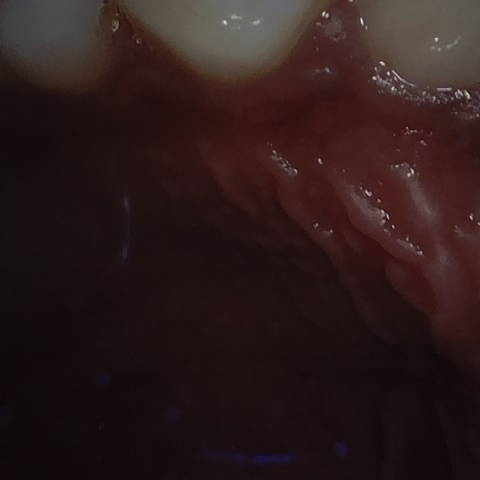

Annotated as "Good"